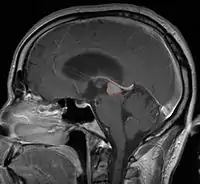

< Radiation Oncology < CNS

Pineal Gland Tumors

Clinical Presentation

• Determined by the spatial anatomy and direction of growth

• Obstruction of aquaduct: hydrocephalus presenting as headaches, nausea, vomiting

• Compromise of superior colliculus: vertical gaze palsy, pupillary and oculomotor nerve paresis (Parinaud syndrome)

• Progressive growth: cranial nerve neuropathies, hypothalamic dysfunction